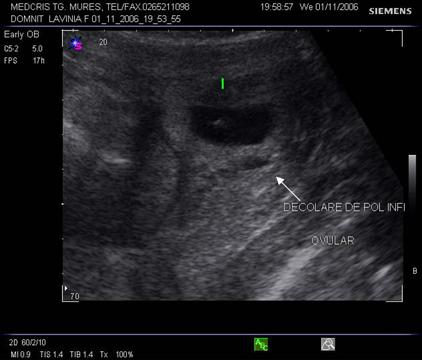

Fig nr 68 Decolare de pol inferior la ecografia abdominala ( sageata )

hematomul mic de sinus marginal (evident ca o decolare anecogena) la polul inferior al sacului gestational are prognostic relativ bun

zona hipoecogena intre peretele uterin si chorion, separata de decidua , indica un hematom subchorionic, cateodata mimeaza o sarcina multipla